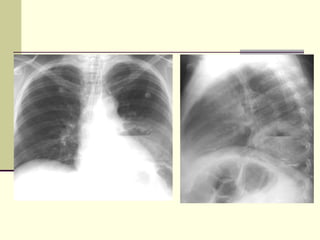

PLEURAL EFFUSION Homogenous density  Meniscus maximum in axilla  Loss of cardiophrenic angle  Loss of diaphragmatic and right cardiac silhouette

MASSIVE  PLEURAL EFFUSION Massive  Shift of mediastinum

PLEURAL EFFUSION Homogenousdensity Meniscus maximum in axilla Loss of cardiophrenic angle Loss of diaphragmatic and right cardiac silhouette

MASSIVE PLEURALEFFUSION Massive Shift of mediastinum